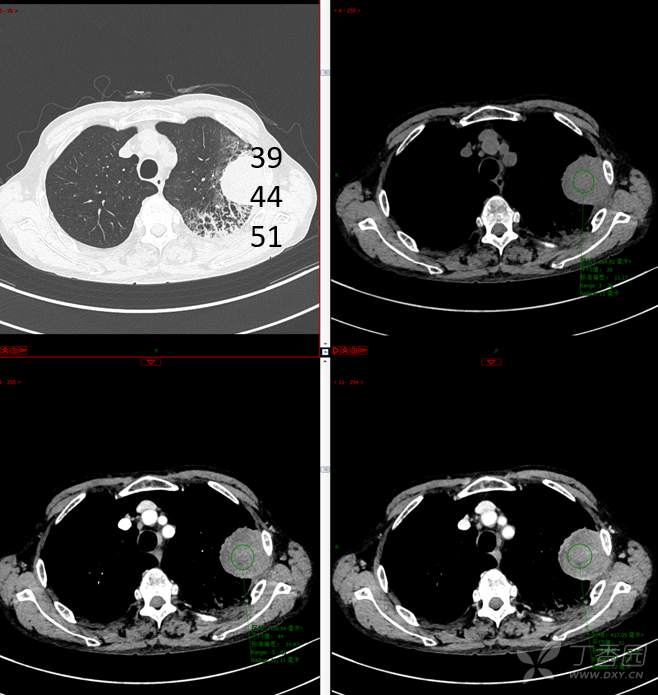

现病史:患者自诉5月前无明显原因及诱因出现纳差、乏力,伴进食后腹胀,无腹痛、腹泻、发热、盗汗、恶心、胸闷,未行特殊处理。1月前无明显原因诱因出现咳嗽,呈阵发性,咳白痰,痰中带鲜红色血丝,10余口/日,无血块,仍伴纳差、乏力、进食后腹胀,无恶心、呕吐、呕血,无头晕、心慌、喘憋、胸闷。在家未行特殊治疗,来我院就诊,2022.8.18行胸部(肺)CT平扫:左上肺占位并左侧肋骨骨质破坏,考虑间叶源性恶性肿瘤。门诊以“肺肿物”收入我科。患者自发病以来,神志清,精神可,饮食差,睡眠可,二便正常,近3月减轻5Kg。